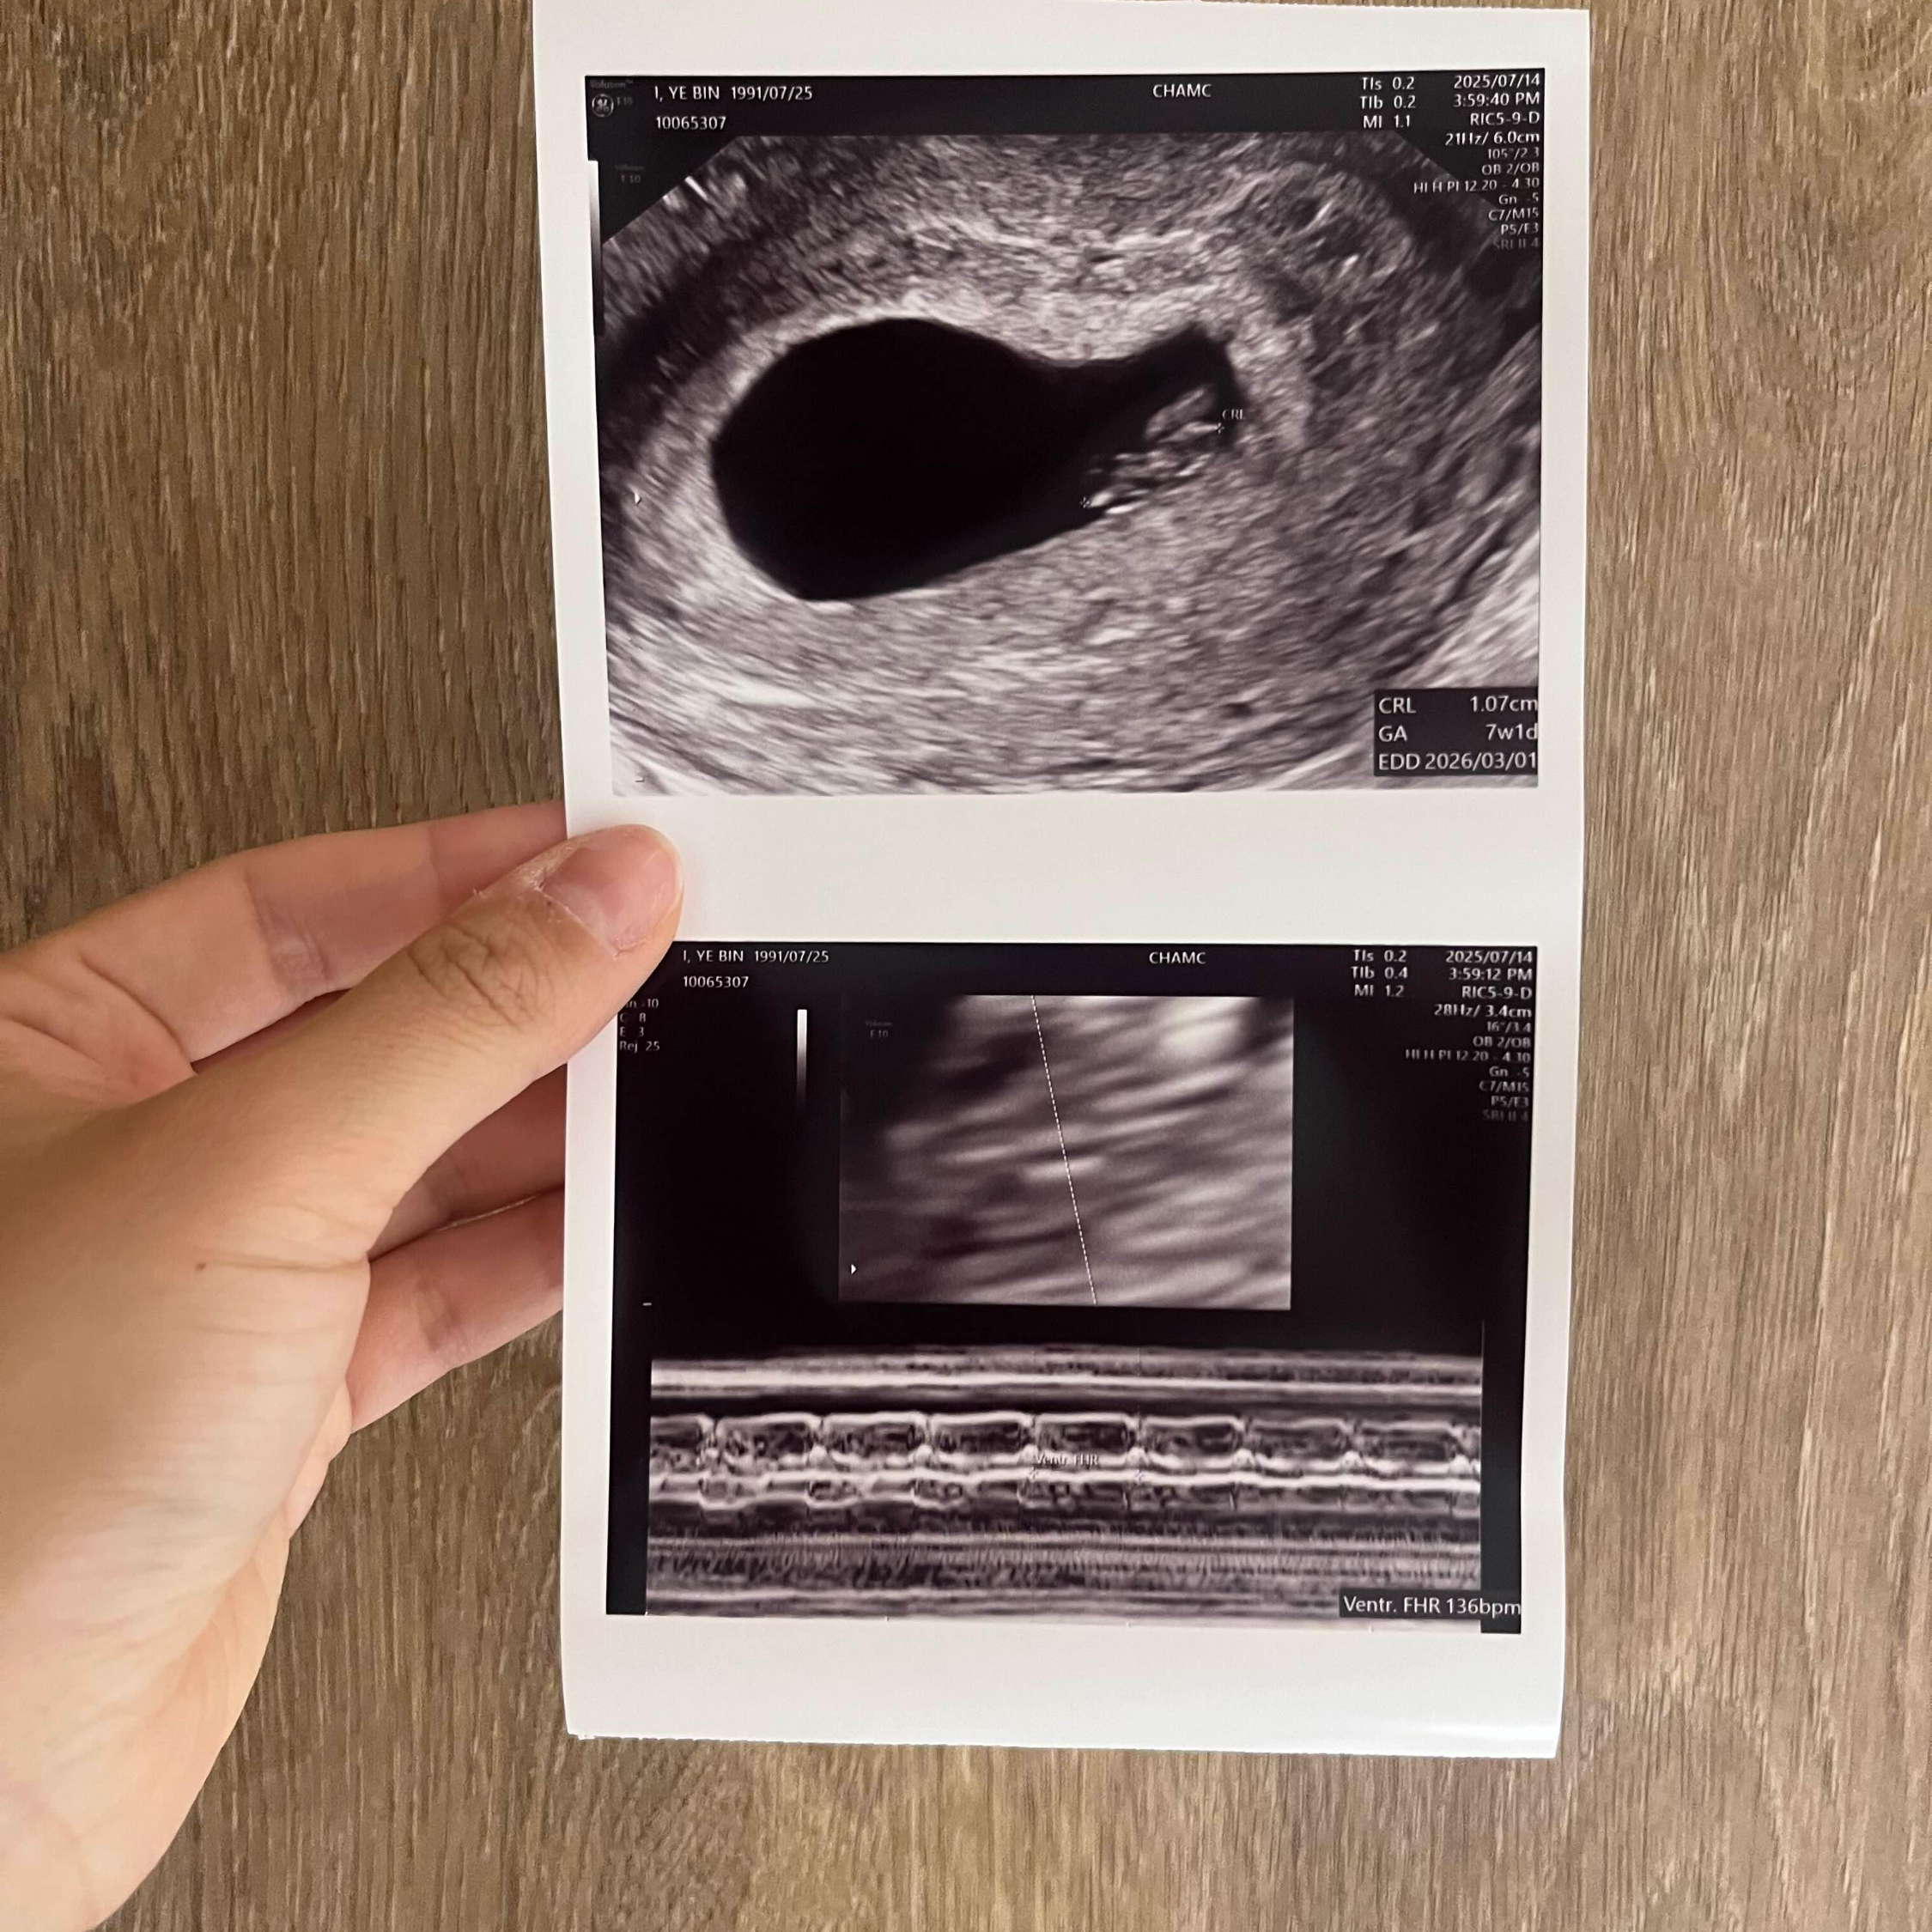

어느덧 7주차가 되었고, 이제 완주는 블루베리만한 크기라고 한다! 신기해.. 이제 눈도 생기는 시기인가?

7주차! 이 날은 뭔가 머리와 몸통이 생긴 완주를 보았다. 그리고 심박수도 체크할 수 있을 정도로 심장이 뛰어서 너무 신기했다. 주수에 맞게 잘 크고 있고, 이젠 아기집도 제법 넓어진 걸 보니 진짜 몸 조심해야겠다는 생각이 들었다. 노 스트레스.. 해피 예삔~~ 해피 완주~~